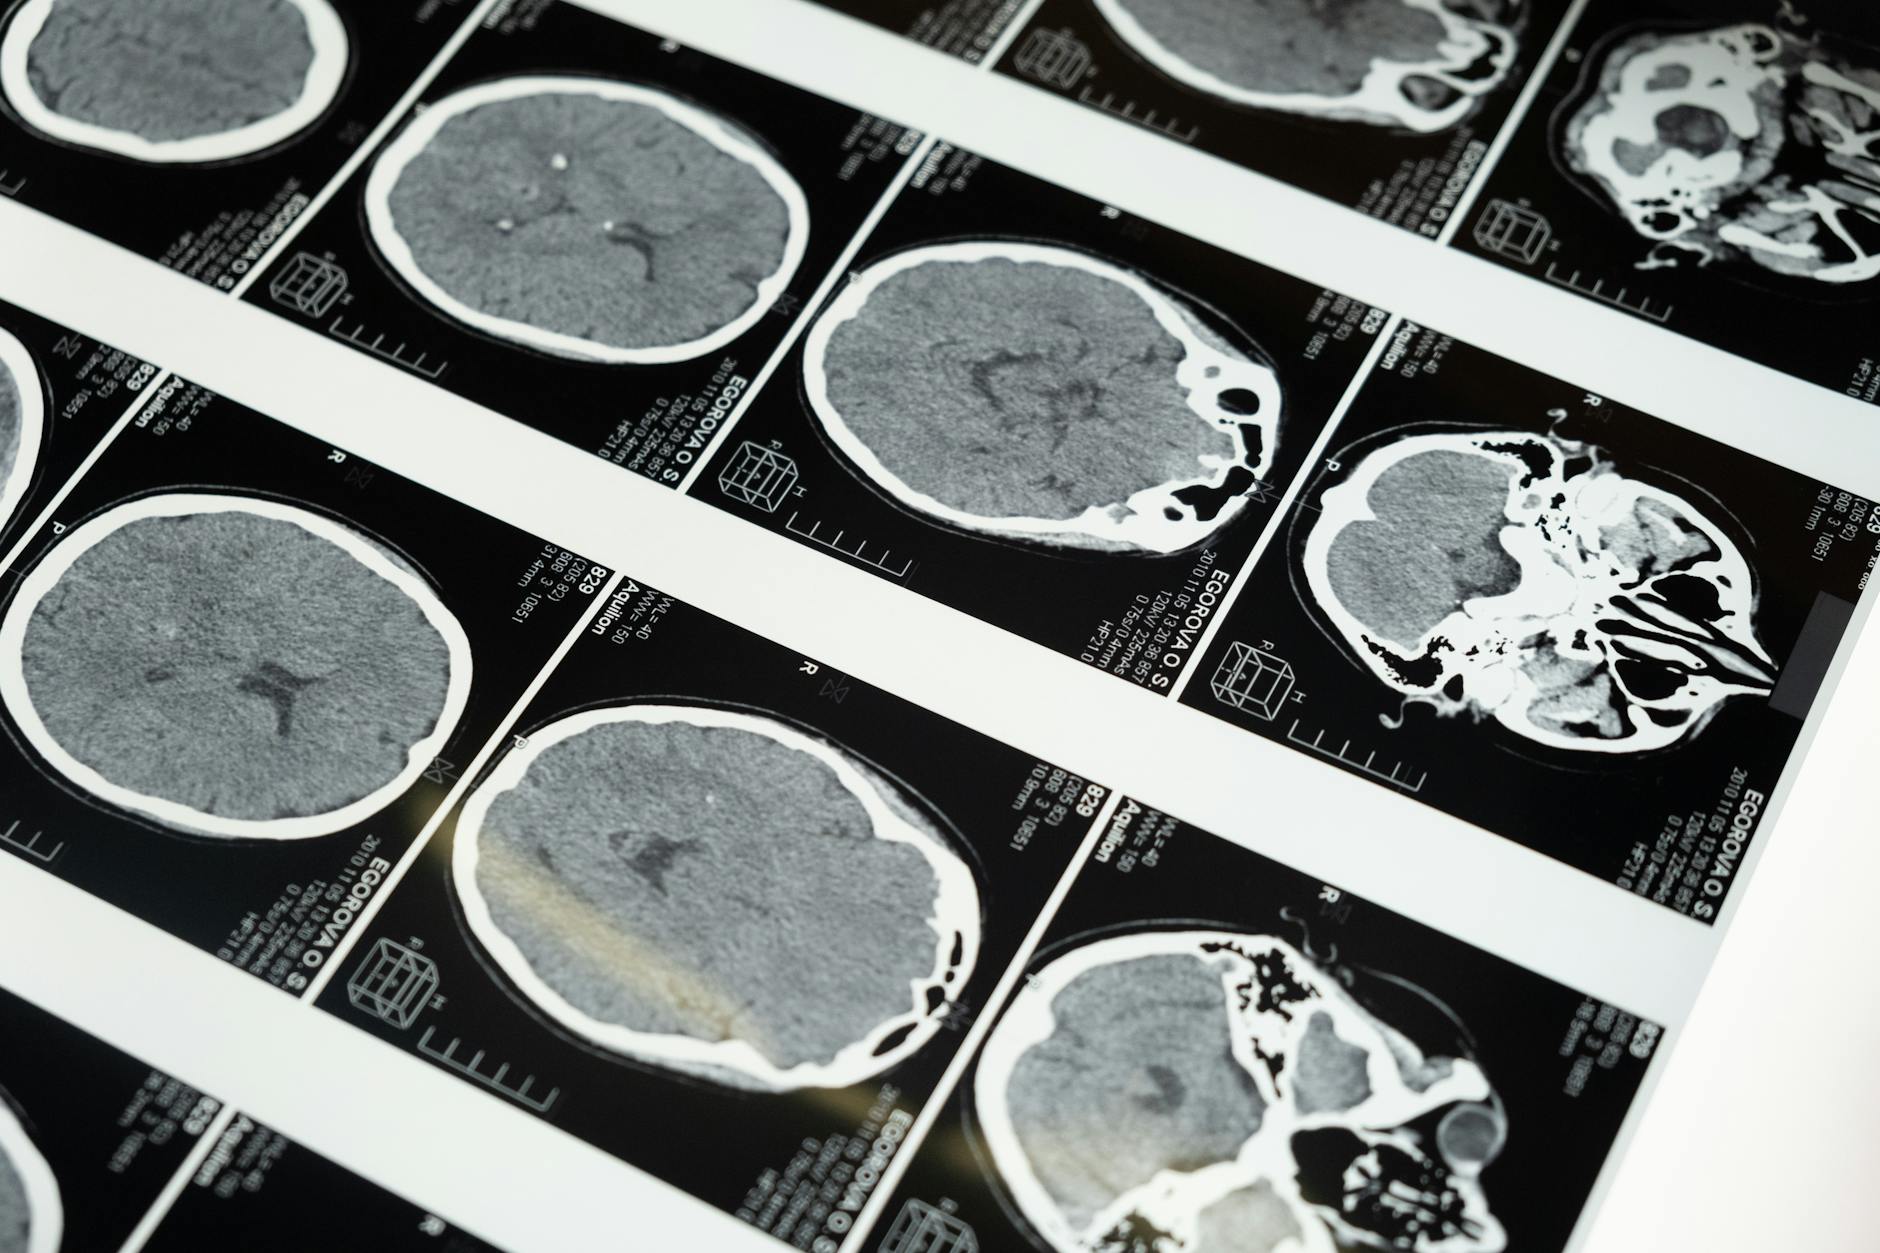

La investigación neurocientífica ha revelado que los TCA están asociados con cambios significativos en la estructura y función del cerebro. Por ejemplo, estudios de neuroimagen han demostrado alteraciones en áreas del cerebro relacionadas con la regulación del apetito, el control emocional y la percepción del cuerpo. Estas alteraciones pueden contribuir a los síntomas característicos de los TCA, como la restricción extrema de la ingesta de alimentos, los atracones y la preocupación obsesiva por el peso y la imagen corporal.